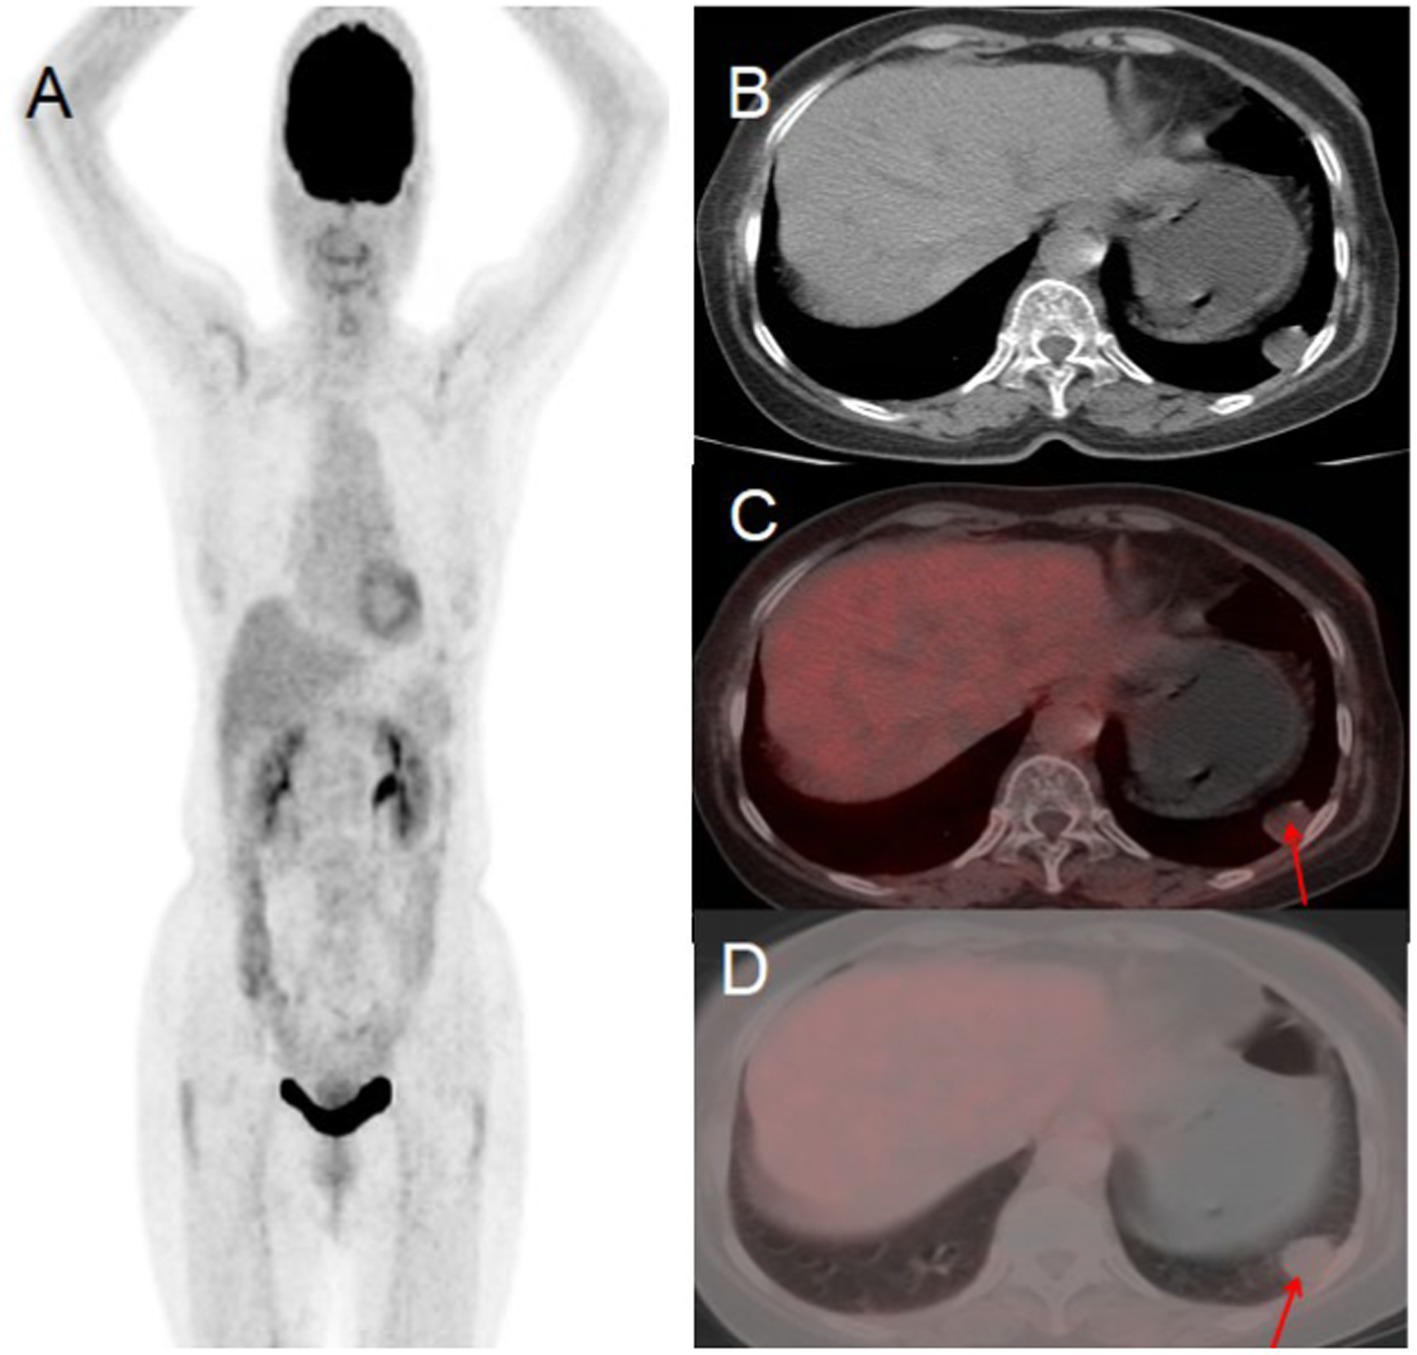

A 76-year-old woman presented to the hospital on November 10, 2022, with a 10-day history of persistent chest tightness. She denied experiencing chest pain, hemoptysis, blood-streaked sputum, fever, night sweats, fatigue, palpitations, heart flutter, chest discomfort, headache, dizziness, nausea, vomiting, diarrhea, or black stools, the patient had no history of chronic disease and a history of other types of tumor. For further evaluation and management, she was admitted to Jiangxi Provincial People’s Hospital. Her tumor markers were all within the normal range. Chest CT revealed a round, soft-tissue-density lesion in the left lower lobe of the lung, which showed mild enhancement on contrast imaging, suggestive of a benign tumor. PET/CT demonstrated a round lesion in the left lower lobe with mild FDG uptake, similar to the background FDG uptake of the adjacent lung tissue. Based on the PET/CT findings, the preoperative diagnosis was a benign lung tumor. After a multidisciplinary team discussion, surgical resection was recommended. Postoperative pathology confirmed a benign solitary fibrous tumor of the lung (see Figure 4).

Figure 4

Female, 76 years old, benign primary pulmonary solitary fibrous tumors. (A) Whole body MIP. (B) Axial CT. (C) Axial fusion. (D) Axial fusion. PET/CT suggested a round lesion in the left lower lobe with mild FDG uptake, comparable to the background FDG uptake of the adjacent lung tissue (arrow, D).